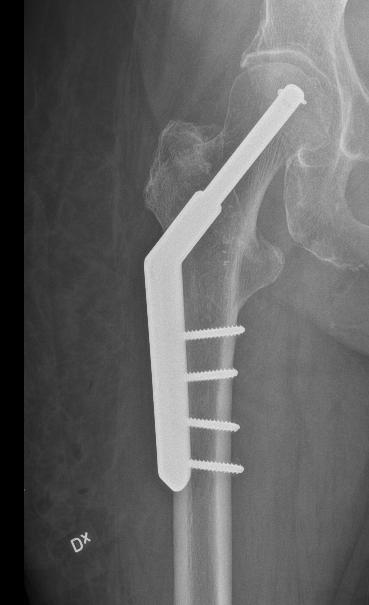

Osteosarkom i thorax som bedömdes som inoperabelt av thoraxkirurger. Dr Thomas Hilton och jag fixade det.

Den kanske viktigaste insatsen är nog ändå mitt arbete som klinisk mentor vid sarkomsektionen i Kapstaden. Jag hjälper till med operationer två dagar i veckan och har mottagning 1-2 dagar. Övrig tid använder jag till registerarbete. Då jag närvarar i den kliniska vardagen så kan jag bidra med min erfarenhet och får lära mig om de svårigheter och fattigdom som de flesta patienter lever i. Att bemästra smärtor, funktionsförlust och oro inför framtiden under sådana omständigheter är oerhört svårt. Hilton och jag har gjort den första van Ness rotationsplastik i Sydafrika som fick pryda första sidan i tidningen Cape Times. Vi har också opererat ett enormt osteosarkom i thoraxväggen som thoraxkirurgerna sa var inoperabelt – men det var det inte.

Professor i ortopedisk onkologi Tema akut och reparativ medicin Karolinska Universitetssjukhuset Femåring från Angola med stort osteosarkom i femur. Tatuering utförd av "natural healer" hos flicka med osteosarkom i proximala femur. Enorm jättecellstumör. Sjukhuset i Windhoek, Namibia. Observera att ortopeden är enda kliniken som nämns på skylten.